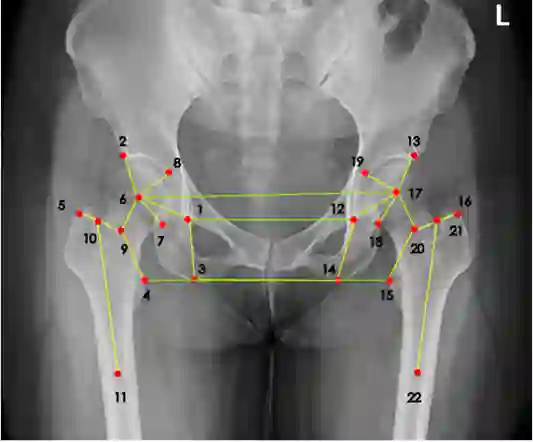

那么有没有可能通过某些自动化方法或者软件来完成准确而且标准的髋关节置换规划?答案是可行的。2018年左右,来自约翰霍普金斯大学的学者曾经提出通过两阶段卷积神经网络结构(CNN)来检测X射线成像图谱的手术测量标志点,并且能够从任意角度来完成成像检测。同时,也有有其他的一些研究试图引入人体解刨学特点,通过找到原本手术测量标志点之间的关系自动标注。但是在实践环节中,这些方法的准确率相较传统方案,并没有提升太多。

达摩院团队认为,医疗图像里不仅仅可以检测标志点,而且能同时自动学习这些手术测量标志点之间的关系,比如可以通过添加一个标志点的空间关系损失函数,来获得更加精确且高效的手术测量标志点检测结果。这种思想也就是把传统神经网络分别为两个支路:一个标志点预测分支,另一个边缘预测分支。在这种思想下,图像会先通过神经网络处理,再分别输入两个分支做不同目的的推理。其中标签预测分支将会把神经网络处理过后的高维特征转换为热点图,而边缘预测分支将会把神经网络处理过的边缘高维特征降维,此后向量化的标记将会提取更好的特征,这样可以通过一个专门针对标识空间位置建立的损失函数来提高边缘标签预测的准确度。